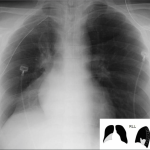

LEFT UPPER LOBE ATELECTASIS

The archive below organizes different examples of a left upper lobe atelectasis. It will really be the anatomical location of the finding that will help diagnosis this SPECIFIC subtype of atelectasis. Click on the thumbnails below to view the archive.

LEFT LOWER LOBE ATELECTASIS

The archive below organizes different examples of a left lower lobe atelectasis. It will really be the anatomical location of the finding that will help diagnosis this SPECIFIC subtype of atelectasis. Click on the thumbnails below to view the archive.